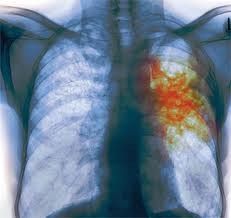

Эозинофильные инфильтраты

Эозинофильные инфильтраты являются состоянием аллергической природы, их причина появления не всегда может быть распознана. Такое заболевание может долго себя не проявлять либо сильно напоминать очаговую пневмонию. Иногда наблюдаются кашель, одышка, боли в груди, достаточно высокая температура.

Очаги легко определяются на рентгеновских снимках, они могут быть множественными либо одиночными, могут менять расположение. Читать далее